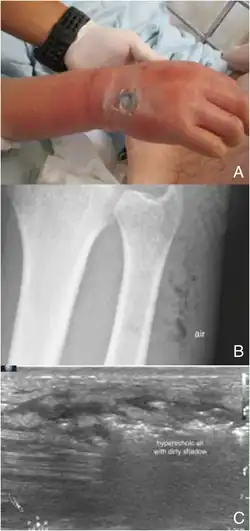

Necrotizing fasciitis is ideally a clinical diagnosis based on symptoms. Due to the need for rapid surgical treatment, the time delay in performing imaging is a major concern.[15] Hence, imaging may not be needed if signs of a necrotizing infection are clear. However, due to the vague symptoms associated with the earlier stages of this disease, imaging is often useful in clarifying or confirming the diagnosis.[15]

Point-of-care ultrasound (POCUS) may be useful in the diagnosis of NF if MRI and CT are not available.[18] It can also help rule out diagnoses that mimic earlier stages of NF, including deep vein thrombosis (DVT), superficial abscesses, and venous stasis.[18] Linear probes are generally preferred for the assessment, especially in the extremities.[18]

Findings characteristic of NF include abnormal thickening, air, or fluid in the subcutaneous tissue.[18] This can be summarized as the mnemonic "STAFF" (Subcutaneous irregularity or Thickening, Air, and Fascial Fluid).[18] The official diagnosis of NF using ultrasound requires "the presence of BOTH diffuse subcutaneous thickening AND fascial fluid more than 2 mm."[18] Gas in the subcutaneous tissue may show "dirty acoustic shadowing."[15] However, similar to other imaging modalities, the absence of subcutaneous free air does not definitively rule out a diagnosis of NF, because this is a finding that often emerges later in the disease process.[18]

Of note, the quality and accuracy of POCUS is highly user-dependent. It may also be difficult to visualize NF over larger areas, or if there are many intervening layers of fat or muscle. It is still unclear whether POCUS improves the speed of diagnosis of NF, or if it reduces the time to surgical intervention as a whole.[18]

Plain radiography (X-ray)

It is difficult to distinguish NF from cellulitis in earlier stages of the disease using plain radiography.[15] X-rays can detect subcutaneous emphysema (gas in the subcutaneous tissue), which is strongly suggestive of necrotizing changes. However, air is often a late-stage finding, and not all necrotizing skin infections create subcutaneous emphysema. Hence, radiography is not recommended for the initial diagnosis of NF.[15] However, it may be able to identify the source of infection, such as foreign bodies or fractures, and thus aid in subsequent treatment.[15]